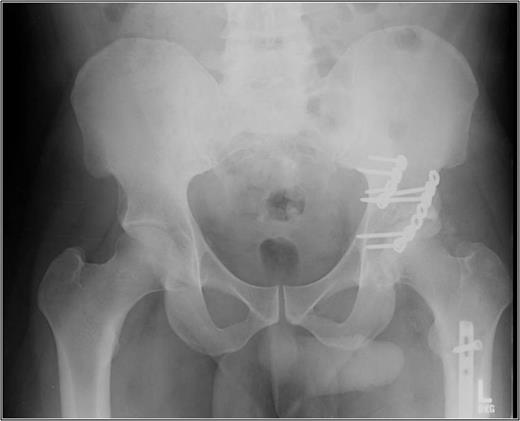

A 35-year-old male was involved in a high-speed urban dirt biking accident. The patient was stable with a GCS of 15 and was neurovascularly intact. His left knee exhibited a 10 × 20 cm medial traumatic arthrotomy and his thigh compartments were soft and compressible. Imaging revealed a left hip postero-superior dislocation, posterior wall acetabular fracture, ipsilateral transverse femoral diaphyseal fracture and an engaging hill-sachs-type lesion of the femoral head with the postero-superior acetabulum (Figs 1–3). Cefazolin, gentamicin and tetanus prophylaxis were administered along with a bedside washout of the traumatic arthrotomy. The patient was medically cleared for operative intervention as all blood work and further imaging were normal.

AP left hip demonstrating a diaphyseal transverse femur fracture with ipsilateral hip dislocation.

AP left femur of type B floating hip with associated hip dislocation. The medial knee soft tissue injury is also appreciated.